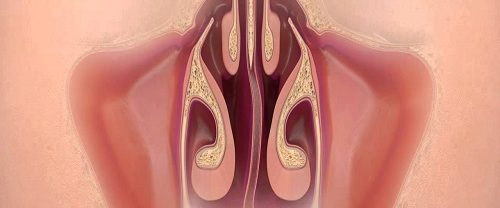

Septoplasti Ameliyatı Nedir? Septoplasti ameliyatı, burun içerisinde yer alan septum adı verilen kıkırdak ve kemik duvarın düzeltilmesi için yapılan cerrahi bir işlemdir. Septum, burun boşluğunu sol ve sağ olmak üzere iki bölüme ayıran kıkırdak ve kemikten oluşan bir yapıdır. Normalde, septum burun deliklerinin ortasında olmalı ve burun boşluğunun eşit olarak sol ve sağ kısımlarını ayırmalıdır.…